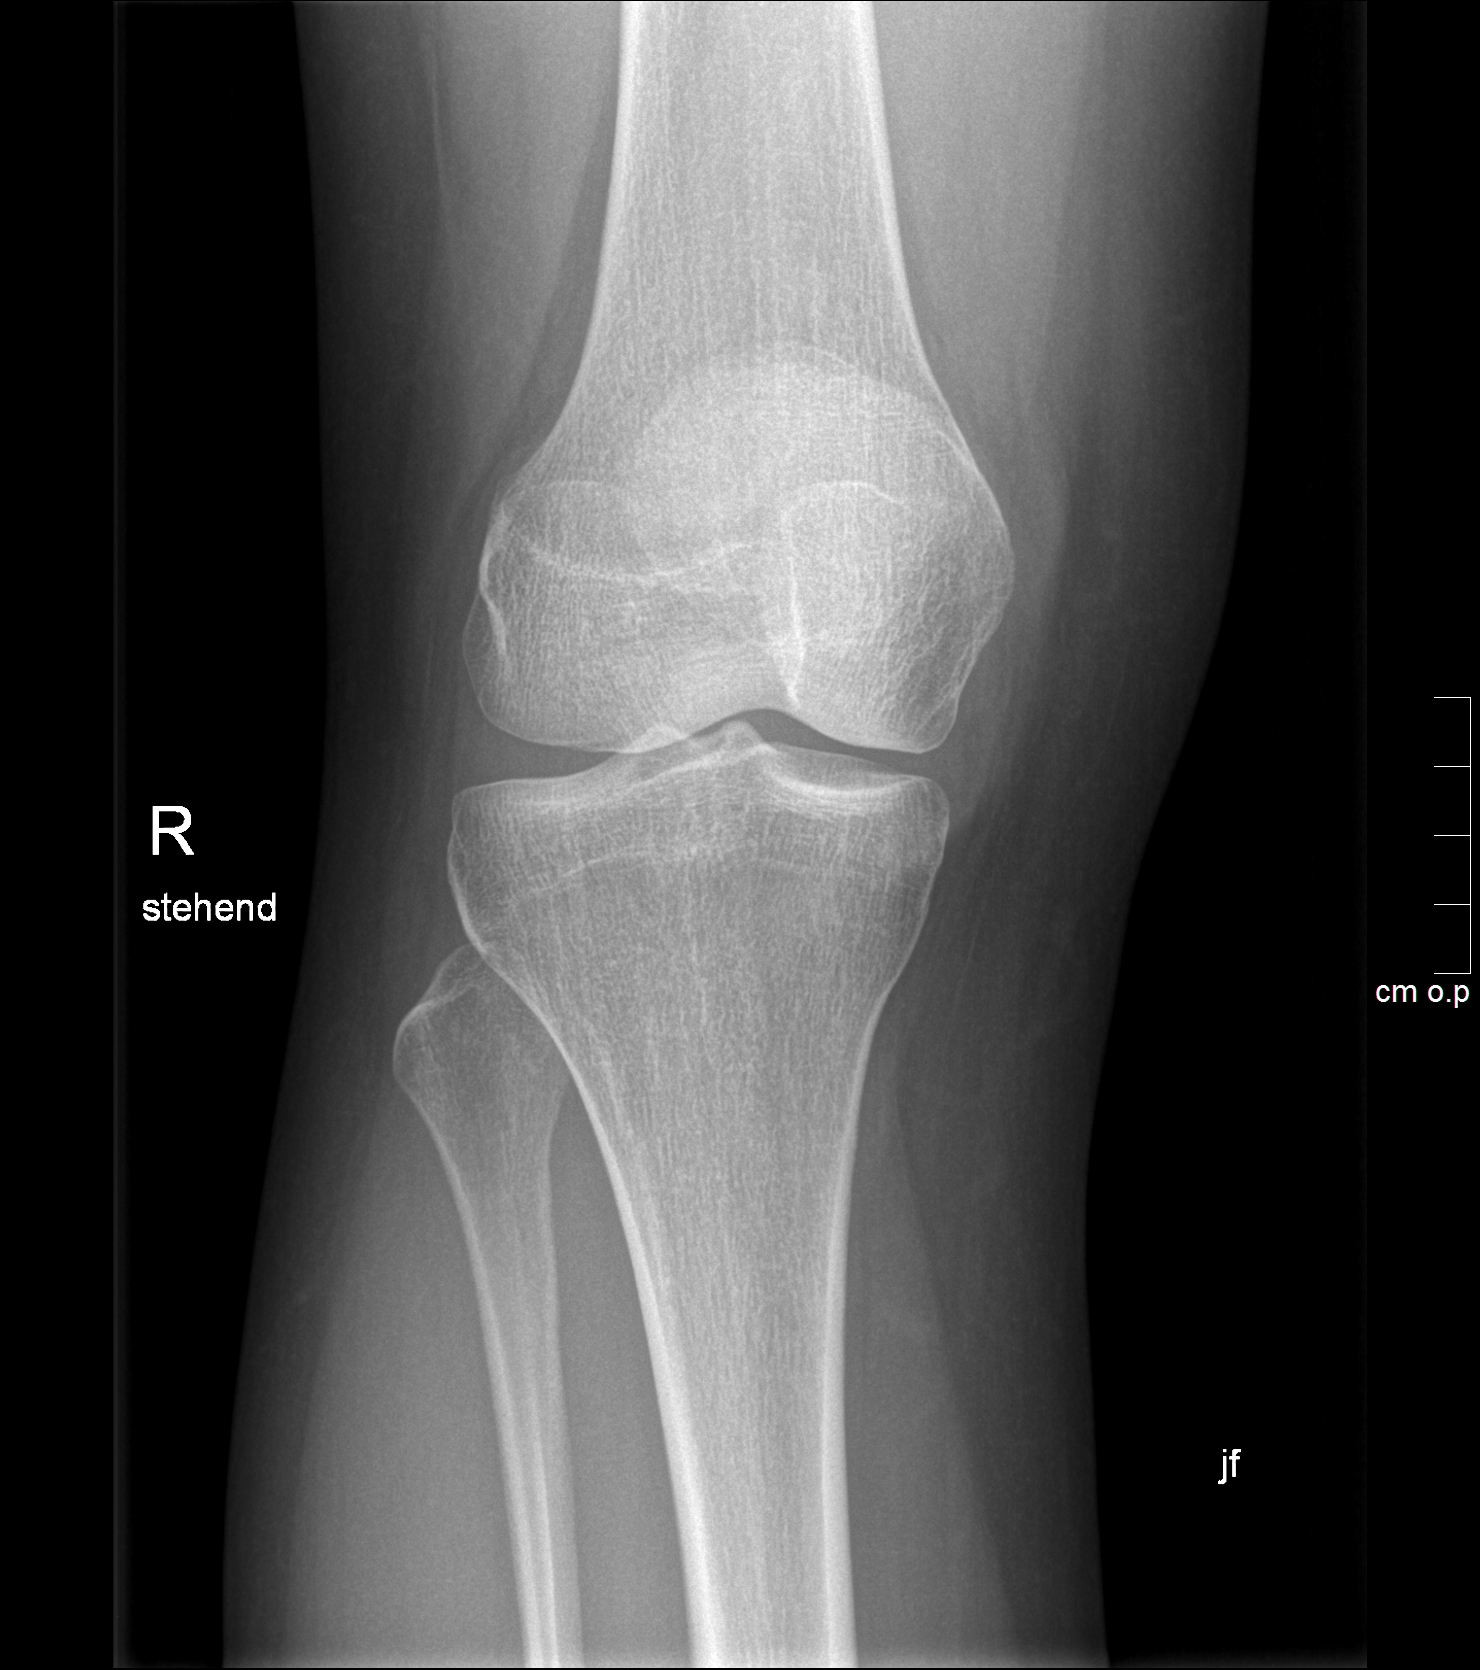

• Ganzbeinstandaufnahme